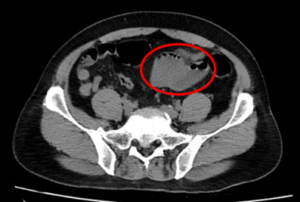

CA LÂM SÀNG: ĐIỀU TRỊ UNG THƯ ĐẠI TRÀNG TÁI PHÁT DI CĂN PHỔI, TUYẾN THƯỢNG THẬN

CA LÂM SÀNG: ĐIỀU TRỊ UNG THƯ ĐẠI TRÀNG TÁI PHÁT DI CĂN PHỔI, TUYẾN THƯỢNG THẬN GS Mai Trọng Khoa, PGS Phạm Cẩm Phương, ThS. Lê Quang Hiển, SV Đỗ Thị Dinh Trung tâm Y học hạt nhân và Ung bướu, bệnh viện Bạch Mai Trường Đại học Y...